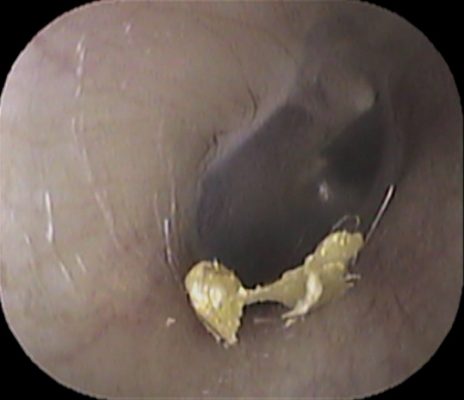

耳垢除去目的で当院受診された子供さんがおられました。

まずは右耳

普通に耳垢があり、除去しました。